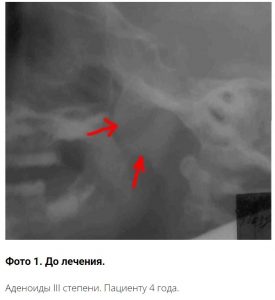

• III степень. Аденоидные разрастания почти полностью блокируют носовое дыхание. Малыш дышит исключительно ртом. Дыхание через рот при увеличенных аденоидах приводит к развитию неправильного прикуса и изменения формы верхней челюсти. Аденоидит вызывает хронический насморк, затруднённости и искажение речи.

Фото рентгенограммы и видео отзывы излеченных пациентов имеются только в нашей клиники и являются собственностью доктора Сичинавы